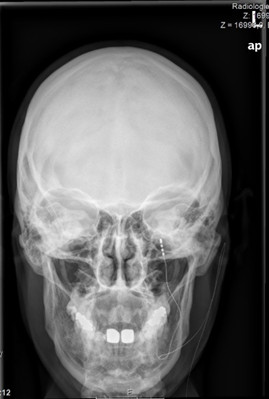

Motorkortex-Stimulation

Bei Schmerzen im Gesicht, die nicht über eine direkte Stimulation des Nerven zu behandeln sind, oder die sich zu großflächig darstellen, besteht die Möglichkeit, direkt den sogenannten Motorkortex zu stimulieren. Zunächst wird der Bereich der Gehirnoberfläche lokalisiert, der die Bewegung des schmerzenden Körperareals steuert. Diese Befunde werden mit einem aktuellen MRT in Einklang gebracht und dienen während der Operation als Landkarte. Es wird nun zielgenau über ein kleines Bohrloch am Schädel eine Elektrode direkt auf die harte Hirnhaut über dem Zielbereich gelegt. Durch eine Hirnstrommessung (EEG) kann die korrekte Lage bestätigt werden. Danach wird ein Stimulator, der die Stimulation dauerhaft steuert, unterhalb des Schlüsselbeins implantiert. Das gesamte System liegt dann unter der Haut. Von außen ist die Stimulation jederzeit veränderbar.